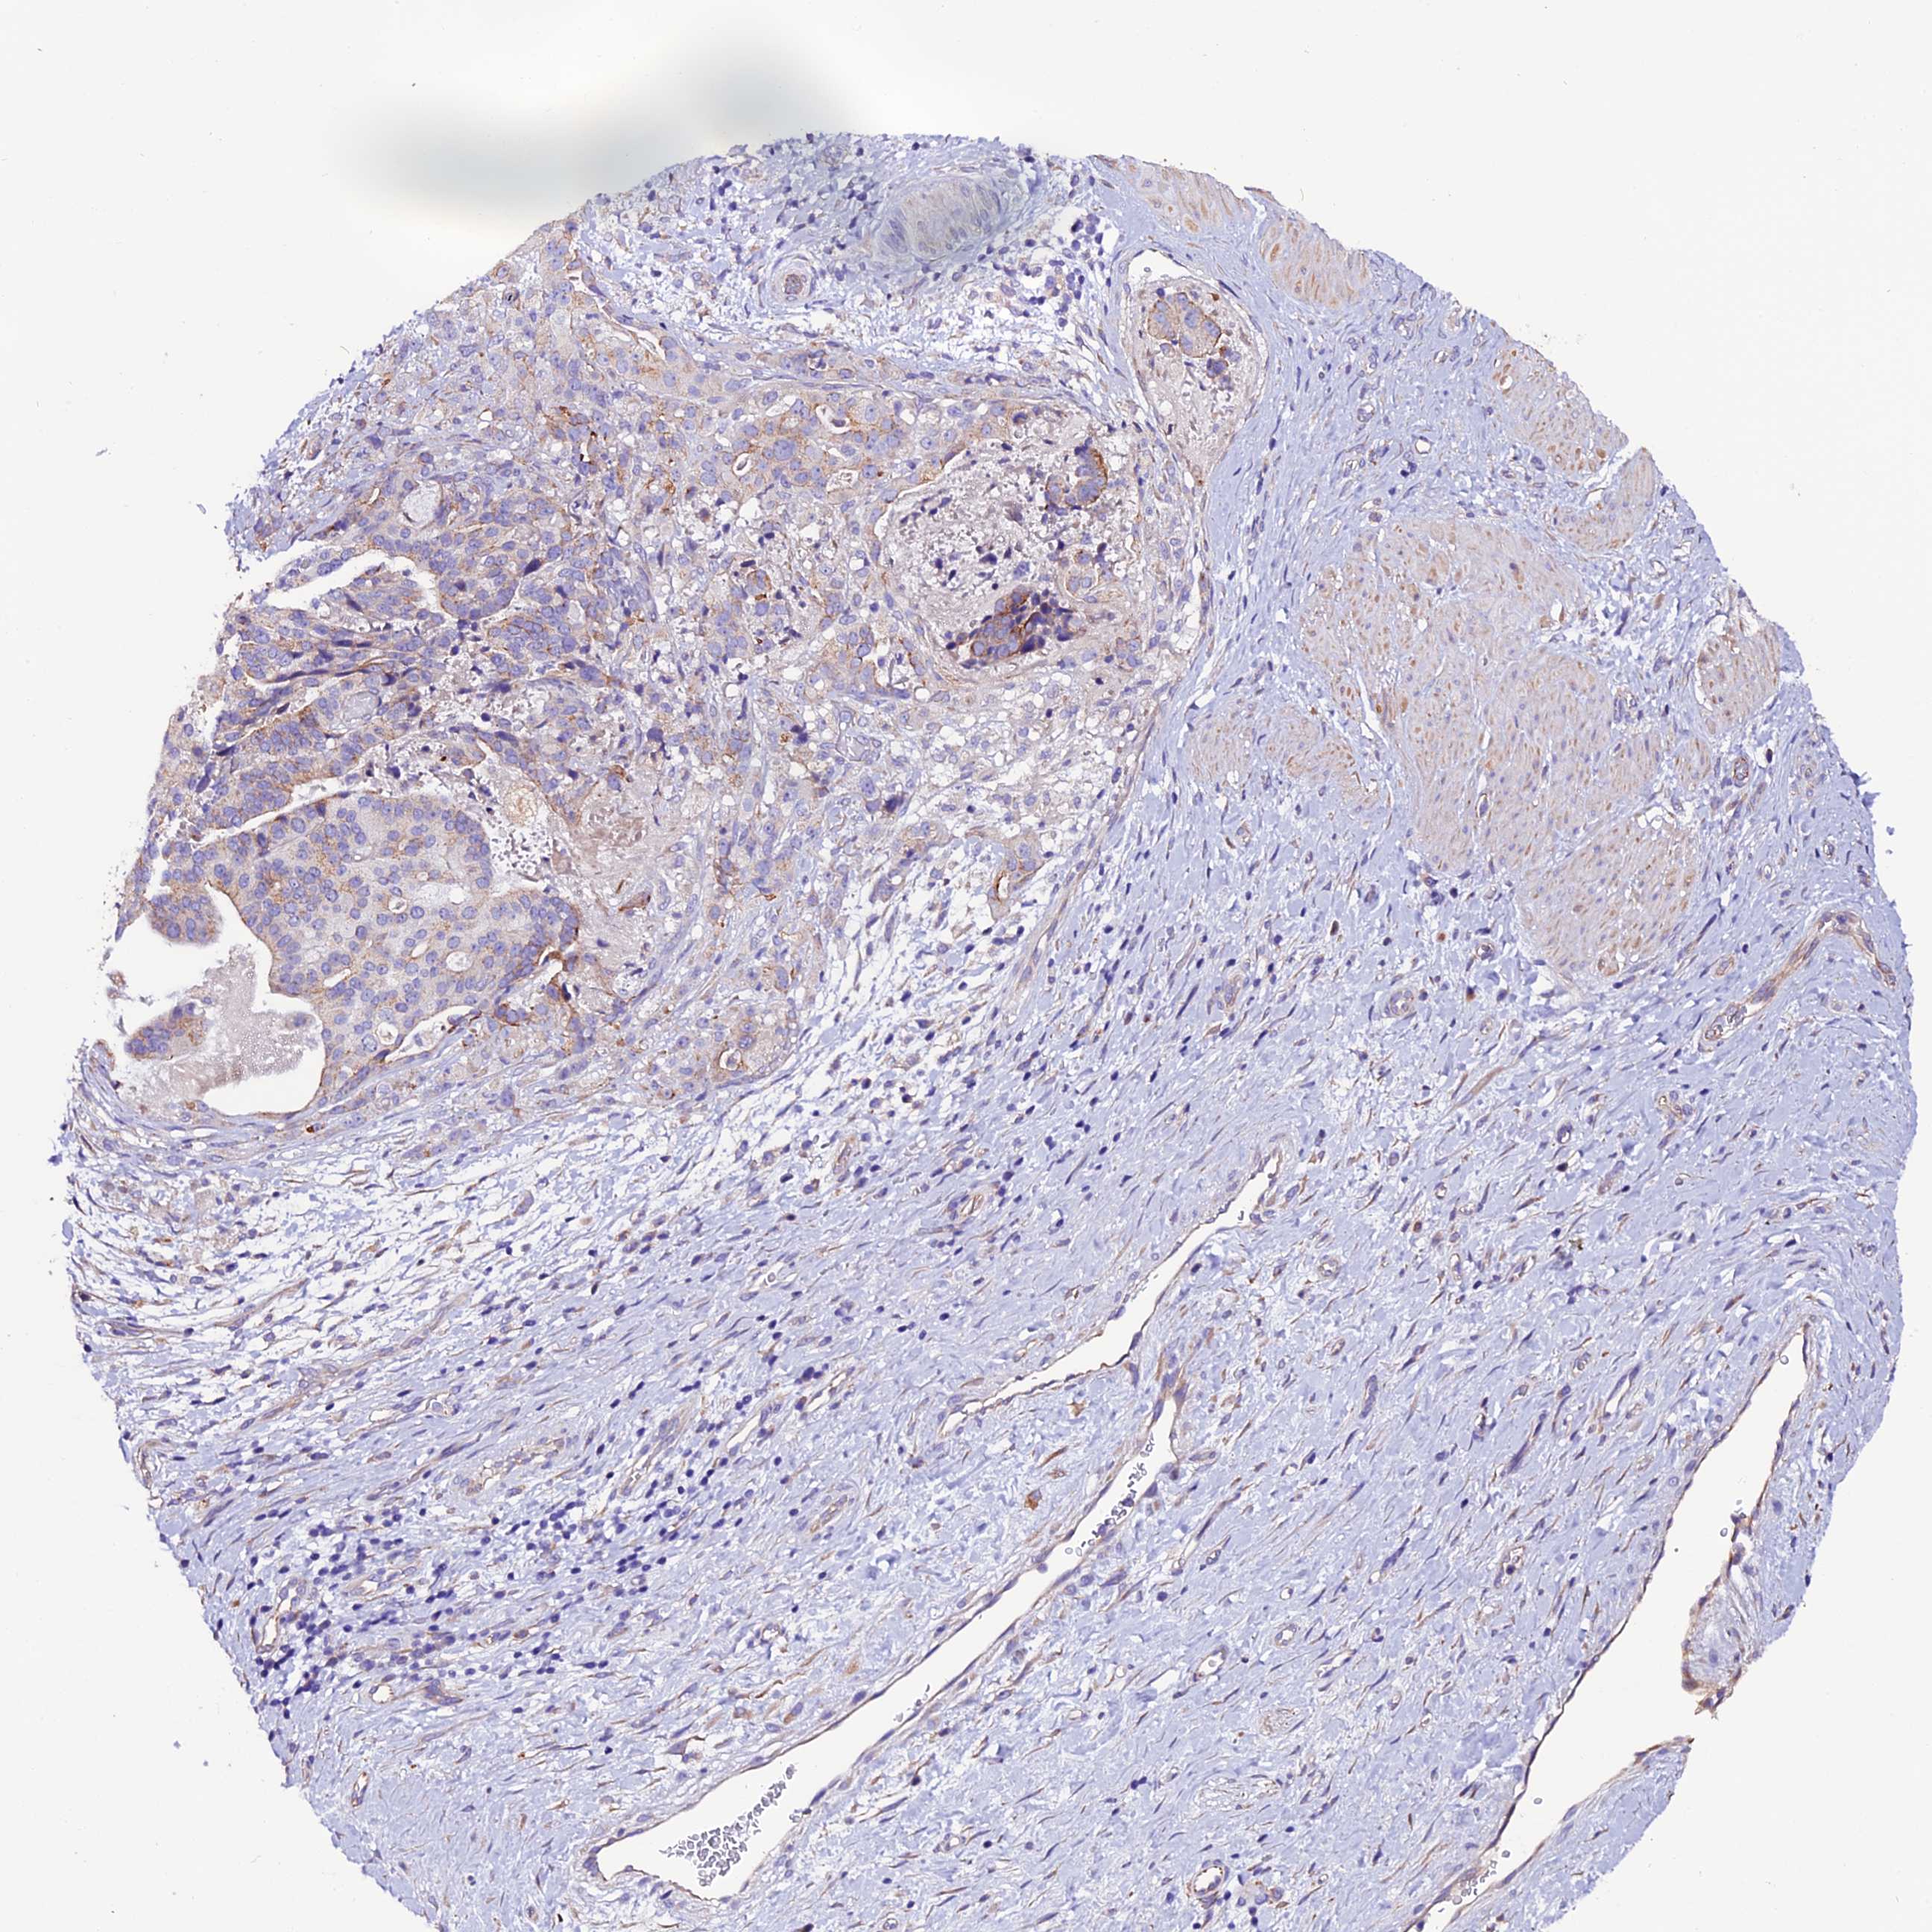

STOMACH CANCER - Protein expressioni

A mouse-over function shows sample information and annotation data. Click on an image to view it in a full screen mode. Samples can be filtered based on level of antibody staining by selecting one or several of the following categories: high, medium, low and not detected. The assay and annotation is described here.

Note that samples used for immunohistochemistry by the Human Protein Atlas do not correspond to samples in the TCGA dataset.

Antibody stainingi

Antibody staining in the annotated cell types in the current human tissue is reported as not detected, low, medium, or high, based on conventional immunohistochemistry profiling in selected tissues. This score is based on the combination of the staining intensity and fraction of stained cells.

Each image is clickable and will lead to virtual microscopy that enables deeper exploration of all samples and also displays staining intensity scores, fraction scores and subcellular localization as well as patient and tissue information for each sample.

Antibody HPA041788

Staining

High

Medium

Low

Not detected

Intensity

Strong

Moderate

Weak

Negative

Quantity

>75%

75%-25%

<25%

None

Location

Nuclear

Cytoplasmic/membranous

Cytoplasmic/membranous,nuclear

Adenocarcinoma, NOS